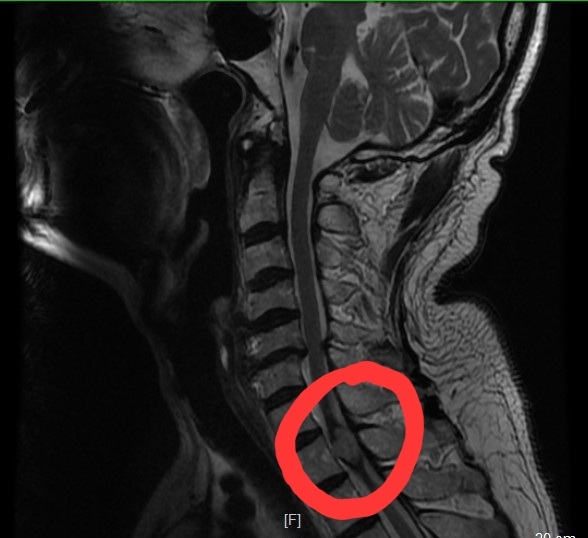

入院核磁共振检查提示T1海绵状血管瘤

术后复查提示海绵状血管瘤全切